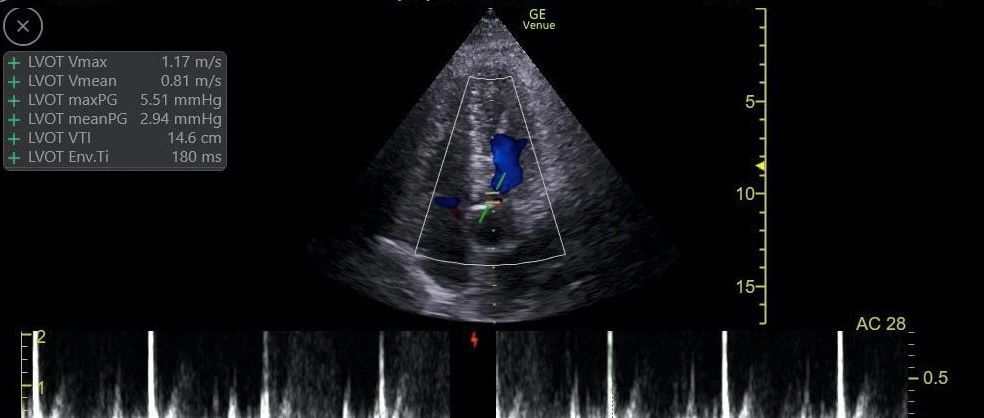

本期我们介绍一个心功能快速变化的患者,一起来解读一下心功能如何变化的呢?01*患者男性,73岁,于09-07在全身麻醉下行胸腔镜中转右开胸右肺上叶切除术,术后于手术室拔除气管插管后出现血氧低,呼吸差,为进一步治疗转入ICU。*9月8日P/F 350. 9mmHg,血流动力学稳定,意识清楚,给予脱机拔管。后因咳痰无力,9月9日16时出现呼吸窘迫,血氧饱和度下降,再次给予经口气管插管,呼吸机辅助呼吸。*后患者出现循环不稳定,阵发性心房颤动,低血压(MAP:55mmHg左右)(大剂量间羟胺联合去甲肾上腺素<2.0ug/kg/min>升压+左西孟旦),LAC进行性增改至6mmol/L,GAP:11,SCVO2:55%,均出现异常,肌钙蛋白明显升高,I、III、 AVF、V7-V9导联ST抬高,予双抗及肝素钠抗凝治疗;患者左心收缩力明显下降,EF在30%以下。积极给予升压强心等综合治疗,患者血压仍无法维持65mmHg以上,且LAC、GAP、SCVO2均未见明显改善。...